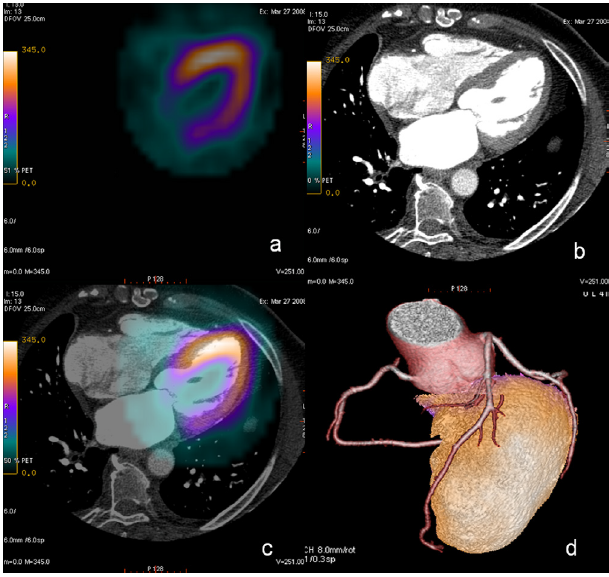

Image

Fig. 8.2 Hybrid methods: Coronarography + CTCA + myocardial perfusion SPECT

• a, b, c (upper line): invasive coronarography

• a: significant right coronary stenosis

• b: revascularization by stent implantation

• c: 50 % non-significant stenosis of the circumflex branch (CX)

• d: CTCA measuring 50 % non-significant stenosis of a specific CX region (intense white spots indicate calcified coronary plaques (confer Ca score))

• e: stress phase of myocardial perfusion SPECT + 3D reconstruction of CTCA demonstrating significant perfusion disturbance in the region of CX: Revascularization is indicated.